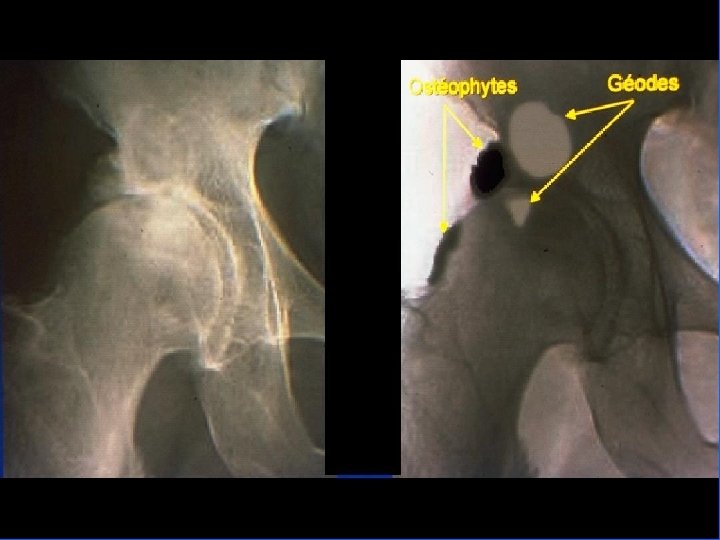

Définition Ø Maladie de l’articulation, caractérisée par: Ø Usure du cartilage (pincement de l’interligne articulaire) Ø Ostéophytose marginale Ø Remaniement de l’os sous-chondral (géodes) Ø Inflammation minime de la membrane synoviale Ø La maladie résulte le plus souvent d’une surcharge mécanique qui aboutit à une authentique maladie biochimique du cartilage.

Coxarthrose Clinique • Debout – Recherche boiterie, – Attitude vicieuse, en flexum ou en rotation externe • Couché – douleur et/ou limitation douloureuse lors mobilisation (flexion / RI / RE) • La radiographie – Cliché bassin debout de face – Profil

Comment faire le diagnostic ? • Le diagnostic est clinique : déformations typiques • Les radiographies : mains de face – pincement de l’interligne – une ostéophytose latérale en berge, très exubérante responsable des nodosités – géodes sous-chondrales